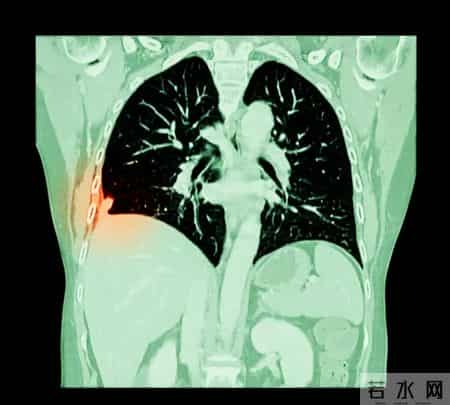

如果你的年龄在50-74岁,并且属于肺癌高风险人群,那么建议每年做一次低剂量螺旋CT,可以降低20%的肺癌死亡率。